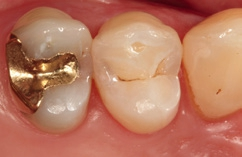

Bei dem 57-jährigen Patienten imponierte in der Routine-Bissflügelaufnahme eine Sekundärkaries an dem mit einem Gold-inlay versorgten Zahn 14 (Abb. 1). Der vitale und symptomfreie Zahn zeigte lediglich radiologisch (Abb. 2) einen Randdefekt distal sowie den Verdacht auf Karies unter dem Befestigungs- bzw. Unterfüllungszement. Nach Entfernung des Goldinlays ergab sich der Verdacht auf eine Pulpaeröffnung (Abb. 3). Klinisch war keine Blutung feststellbar, was allerdings durch die Lokalanästhesie kaschiert sein konnte. Aufgrund der Symptomlosigkeit des Zahnes und fehlender Anzeichen einer Pulpitis (fehlende Blutung) sowie einer Nekrose (erhaltene Vitalität) fiel die Entscheidung zugunsten einer Vitalerhaltung unter Beibehaltung eines engmaschigen Recalls mit Vitalitätsproben. Die Überkappung der Eröffnungsstellen erfolgte als Alternative zu Calciumhydroxid [8] mit einem Portlandzement enthaltenden Flowkomposit mit hohem pH-Wert [7,51] (TheraCal LC, Bisco, Abb. 4). Obwohl dieses Produkt hinsichtlich seiner Effektivität und Zelltoxizität nicht an ProRoot MTA (Dentsply Sirona) und Biodentine (Septodont) [42] herankommt [5,11], ist es hinsichtlich seiner Praktikabilität und der Möglichkeit des sofortigen, zügigen Weiterarbeitens konkurrenzlos. Ein vergleichbares Produkt gibt es z.B. bei Ultradent (Ultra- Blend Plus).